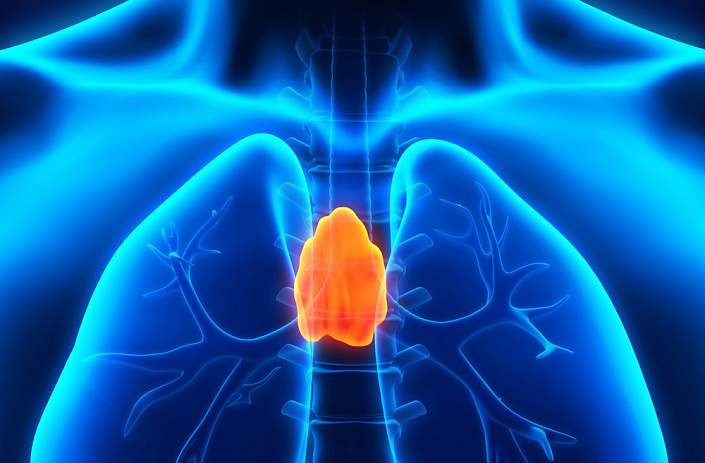

Тимус

Эта эндокринная железа играет определённую роль лишь до момента полового созревания ребёнка, после чего постепенно снижает уровень функциональности, уступая место более развитым и дифференцированным органам. Функцией тимуса является синтез тимопоэтинов — растворимых гормонов, от которых зависит качество и активность иммунных клеток, их рост и адекватная реакция на патогенные процессы. Однако с возрастом ткани тимуса заменяют соединительные волокна, а сама железа понемногу редуцируется.